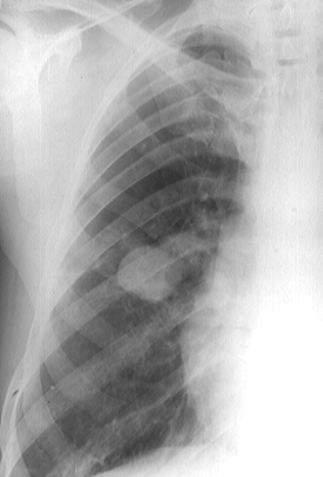

Rx toracică, incidență P-A (centrată pe hemitoracele drept)

DESCRIERE:

în 1/3 sup. a hemitoracelui drept → opacitate de formă triunghiulară, intensitate medie-mare, omogenă

caracter retractil → tracționează traheea și mediastinul de partea afectată + retracția scizurii orizontale (aspect concav)

adenopatii hilare

pahipleurită diafragmatică → îngroșarea pleurei + tracțiuni fibroase

DX: atelectazie prin NBP central endobronșic (pe bronhia lobară sup. dr.)

DD: pneumonie lobară - nu are caracter retractil, prezintă bronhogramă aerică